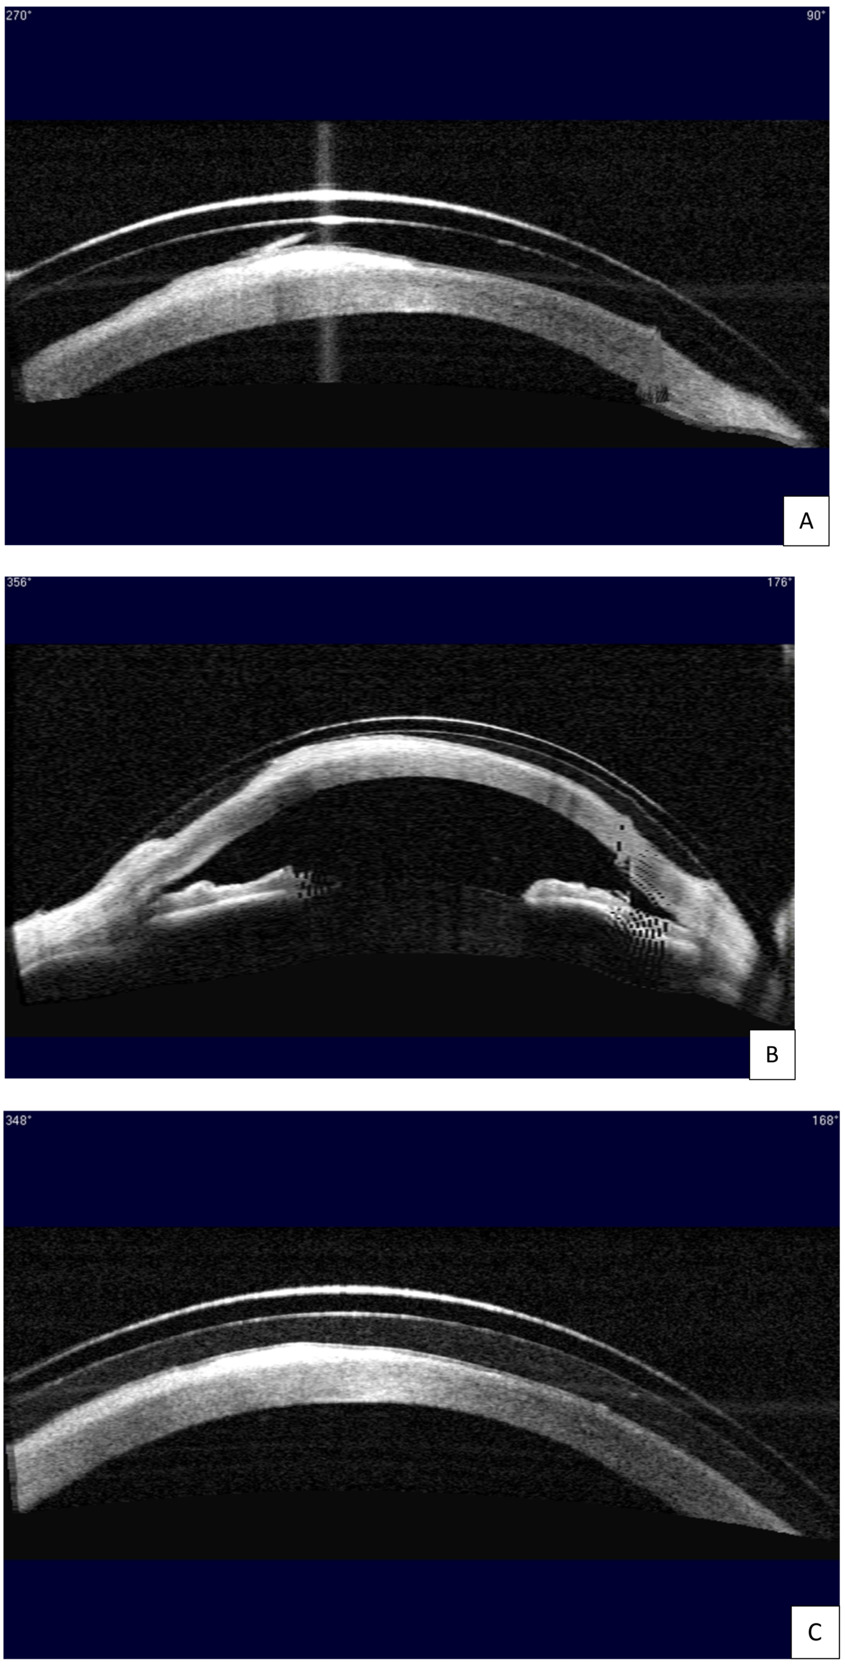

At the initial evaluation, she presented with a distance best corrected visual acuity of 20/60- in the right eye and 20/20 in the left eye with a refraction of -1.25 - 0.50 x 065 right eye and +1.00 sphere left eye. Near visual acuity was 20/50 right eye and 20/20 left eye with +2.50 additional power over the manifest refraction. Slit lamp examination of the anterior segment revealed a large area of horizontal corneal scar tissue across the visual axis with corneal neovascularization temporally in the right eye. The area of the scar tissue stained with sodium fluorescein, indicating active epithelial defects (Figure 1A). Fluoroimaging using the OCULUS Keratograph 5M highlighted the extensive epithelial breakdown over the corneal scar and revealed diffuse 2+ superficial punctate keratitis across the entire corneal surface, more pronounced in the interpalpebral zone (Figure 2A). A few large epithelial defects were oval shaped. Using the Zeiss Visante anterior segment optical coherence tomography, cross-section images of the cornea at all angles confirmed extensive epithelial but minimal stromal involvement in the corneal scar tissue. An example of a corneal cross-section image through the scar tissue is shown in Figure 3A.

At the initial evaluation, the severity of neurotrophic keratitis was graded to be stage II based on the Mackie classification2 and stage 4 based on the Neurotrophic Keratitis Study Group classification,3 since there were oval-shaped epithelial defects present and minimal stromal involvement with no signs of acute corneal ulceration (Figure 2A and Figure 3A).

The right eye was fit with a scleral lens with the goal of improving her overall visual function. Onefit MED (CooperVision Specialty EyeCare – Blanchard) was chosen for its highly customizable parameters for fitting irregular corneas and its thin lens profile that would maximize oxygen transmission. Several diagnostic lenses were trialed on the eye. According to guidelines provided by the laboratory, the ideal diagnostic lens was chosen with a sagittal height that would lead to a central fluid reservoir thickness of ~350 μm immediately on insertion.4 The ideal diagnostic lens had the following parameters: 4400 sagittal height / prolate shape / 15.6 diameter / -1.50 power / 0.25 central thickness / standard midperipheral value / standard limbal value / +75/-75 edge value. Clearance assessment after 4 hours of wear time with anterior segment optical coherence tomography showed ~300-μm central fluid reservoir thickness and ~40-μm fluid reservoir thickness over the epithelial defects and the scar tissue (Figure 3A). Slit lamp evaluation revealed good centration and coverage of the lens without edge lift, compression, or blanching 360. There was an overrefraction of +3.75 sphere with best corrected visual acuity of 20/30. The fit and the vision were deemed acceptable, and the first lens was ordered with the following parameters: 4400 / 15.6 / +2.25 / 0.23 / standard midperipheral value / standard limbal value / +75/-75 edge value /Optimum Infinite material.

At the first follow-up visit on July 21, 2020, her best corrected visual acuity was 20/25 with plano overrefraction in the right eye. Slit lamp assessment continued to show a satisfactory fit. However, clearance assessment with the anterior segment optical coherence tomography revealed an area of touch at 356°, indicating insufficient clearance (Figure 3B). The lack of clearance may cause corneal abrasion and compromise the health of the corneal surface. Therefore, the sagittal height of the scleral lens was raised by 100 μm, and the second right lens with the following parameters was ordered: 4500 / 15.6 / +1.12 / 0.22 / standard midperipheral value / standard limbal value / +75/-75 edge value / Optimum Infinite material.

At the second dispense and follow-up visit on August 3, 2020, the patient had 20/25 best corrected visual acuity with plano overrefraction in the right eye, and an excellent fit was observed with both slit lamp examination and clearance assessment with the anterior segment optical coherence tomography after 4 hours of wear time. The second right lens was dispensed. She was instructed to come back for follow-up every 6 months or sooner if issues occur.

The patient has been wearing the right scleral lens successfully since the August 03, 2020 visit. At the 1-year follow-up on December 22, 2021, she again presented with best corrected visual acuity of 20/25 with no overrefraction in the right eye. She reported clear and comfortable vision all day with scleral lens wear. Clearance assessment with the anterior segment optical coherence tomography showed no touch 360°, with a central fluid reservoir thickness of ~250 μm after 6 hours of wear time (Figure 3C). Slit lamp examination continued to show an excellent-fit relationship. The most striking finding is that 1 year of scleral lens wear significantly improved the severity of neurotrophic keratitis in this patient. When comparing the anterior segment photo on December 22, 2021 (Figure 1B), to the initial photo on July 7, 2020 (Figure 1A), significantly less corneal haze was seen in the horizontal scar tissue across the visual axis, except in a small area inferonasally over the pupil and away from the line of sight at the end of the temporal corneal neovascularization. Moreover, when comparing the fluoroimage on December 22, 2021 (Figure 2B), to the initial image on July 7, 2020 (Figure 2A), all oval-shaped epithelial defects have healed, and only 1+ diffuse superficial punctate keratitis was present on the corneal surface. From July 7, 2020, to December 22, 2021, the severity of her neurotrophic keratitis had improved from stage 2 to stage 1 based on the Mackie classification2 and from stage 4 to stage 2 based on the Neurotrophic Keratitis Study Group classification.3